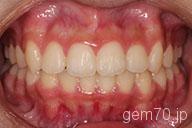

症状:叢生装置:セラミックブラケット | 非抜歯(歯を抜かない)世代:中学生

主訴)歯のでこぼこ

診断)叢生

年齢)14歳

使用装置)マルチブラケット装置

治療方法)非抜歯(歯を抜かない)

治療期間) 2年4ヵ月 通院回数 27回